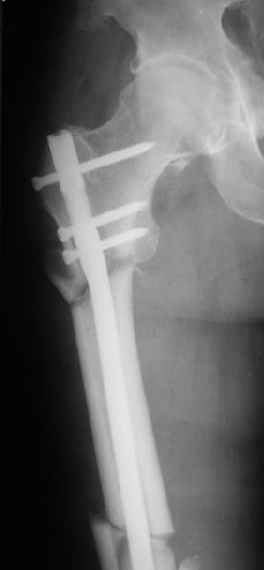

Я пошел на операцию имея стерильным и обычный бедренный гвоздь ChM и реконструктивный.

Когда открыто убрали DHS встали перед выбором, что ставить? Так, как это был подвертельный перелом - поперечная линия на уровне малого вертела то поставили обычный бедренный гвозь и один прокс блокирующий винт, который затянули компрессирующей заглушкой.

В частности, на проксимальном конце сделано еще одно дополнительное статическое отверстие. Можно ввести в проксимальном отделе 4 винта, из них 3 статические (2 в круглые отверстия и 1 по нижнему краю овального). Картинки в приложении. На дистальном конце стержня тоже кое-что улучшено. Спрашивайте в аптеках, как говорится. Выпускается предприятием "ЦИТО" (Москва), то есть это малобюджетное решение.